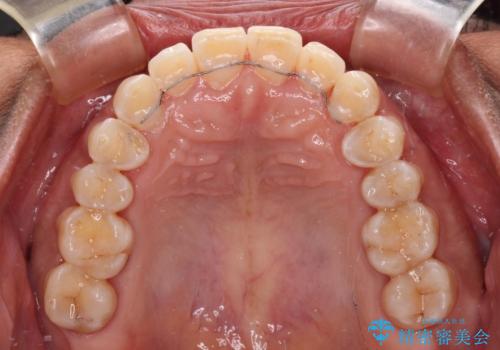

反対咬合の改善 途中で出産をしながらワイヤー矯正

- 矯正装置

- メタルブラケット

- 前歯の隙間と反対咬合を気にして来院された患者様です。

マウスピース矯正も提案しましたが、しっかりと使用する自信がないとのことで、ワイヤー装置により矯正治療を行うこととしました。

咬合力が強く、反対咬合の改善に時間がかかりましたが、その後はスムーズに進めることができました。

途中、妊娠と出産があり、治療が中断したため、治療期間は延びましたが、出産も矯正治療も無事に終えることができました。